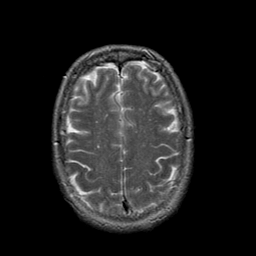

In this study, the dataset introduced in [8], which is publicly available111https://github.com/ChengBinJin/MRI-to-CT-DCNN-TensorFlow, is used for performance evaluation. It consists of 367 paired CT and MR images with the size of 512256. In the original dataset, it is noted that several CT images have stereotactic head frame that was used in Gamma Knife treatment. This head frame manually removed from the CT images. In addition, there exist various CT and MR slices that brings incredible difficulty in training the generator. Therefore, 100 images are selected from similar slices for each modality, in which 90 and 10 images are used for training and testing, respectively. Fig. 5 shows four examples of pre-processed samples.